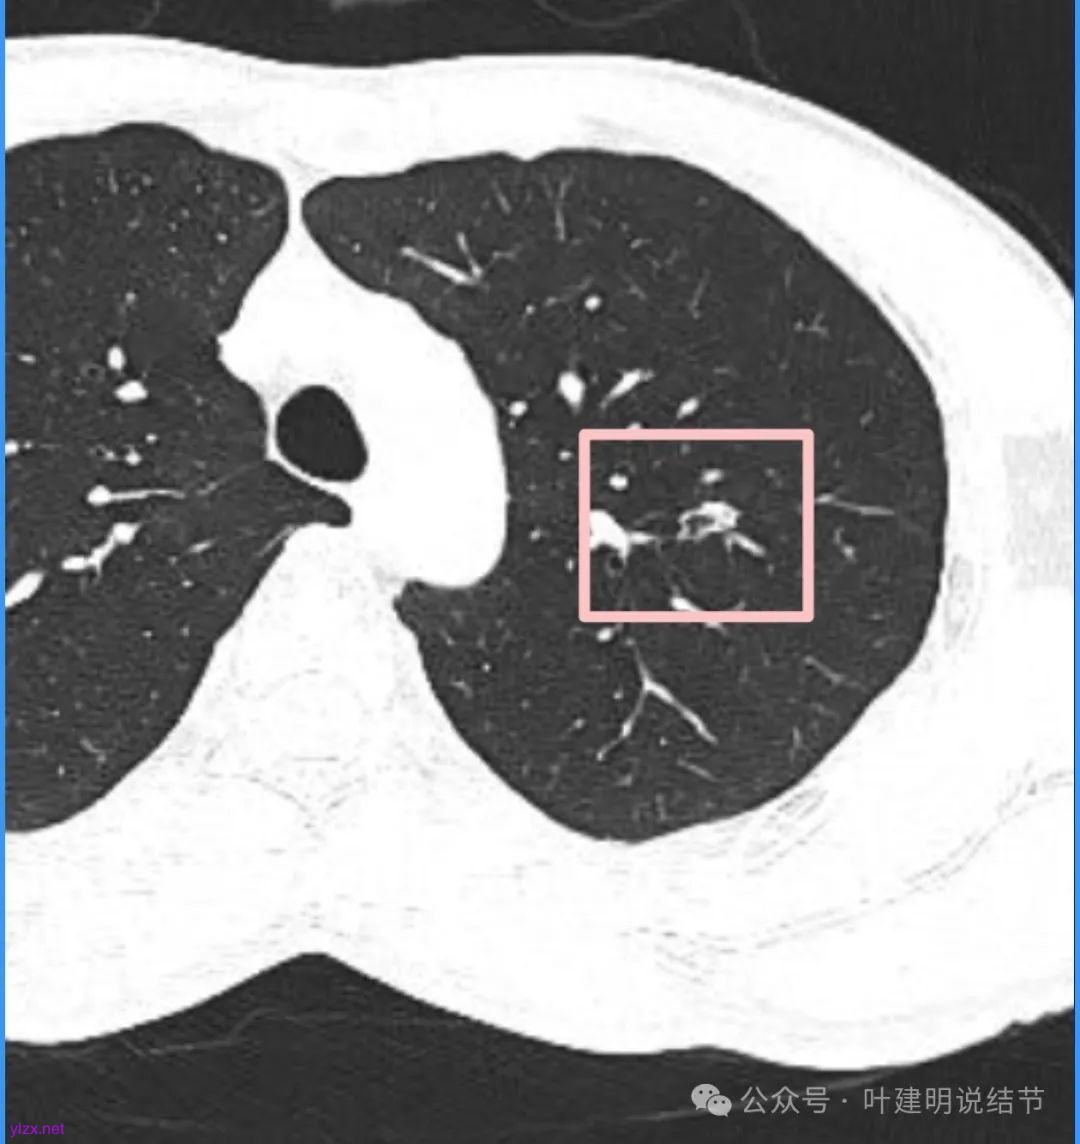

蓝色部分似乎是血管,但似乎又是增厚的支气管壁,局部细支气管扩张。

特别上上图边缘些的层面,蓝色箭头所指的实性明显又像位于扩张细支气管内或与支气管壁一块的样子。

再看看近半年前2024年11月时的影像:

我们发现一是病灶与25年3月的几乎没有区别,二是原来蓝色箭头处不太像血管,而是结节边缘的一部分,而结节灶内又是有扩张支气管的。